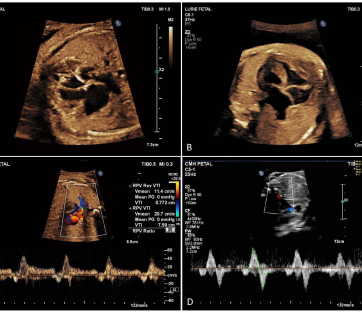

Multivessel Doppler

Multivessel Doppler is a medical imaging technique that uses Doppler ultrasound technology to assess blood flow in multiple blood vessels within the body. It helps healthcare providers decisions patient care

- Ultrasound Probe

- Color Doppler

- Spectral Doppler